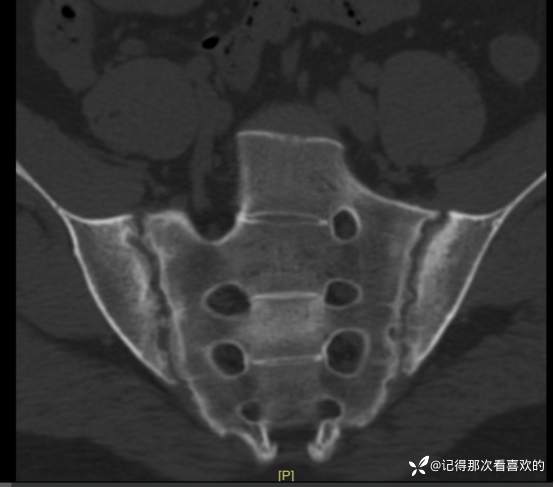

06-04 胸部CT平扫|骶髂部CT平扫:1、双肺下叶少许慢性炎及纤维灶,部分呈间质性改变可能。2、左肺下叶小结节,随诊。3、扫及脂肪肝。4、扫入胸椎椎体毛糙略呈竹节样改变,请结合临床。5、骶髂关节异常改变,考虑骶髂关节炎,强直性脊柱炎可能?请结合临床及相关检查,随诊。

06-05 骶髂关节MRI平扫:1、双侧骶髂关节改变,符合为强直性脊柱炎所致。请结合临床实验室检查结果。2、左髋关节少量积液。请结合临床及其他检查,随诊。